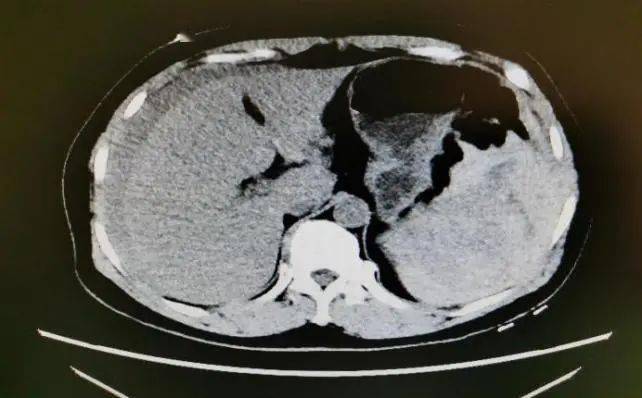

张阿姨腹部ct显示:脾脏破裂,腹腔积血.

【讨论】脾脏ct平扫 增强.